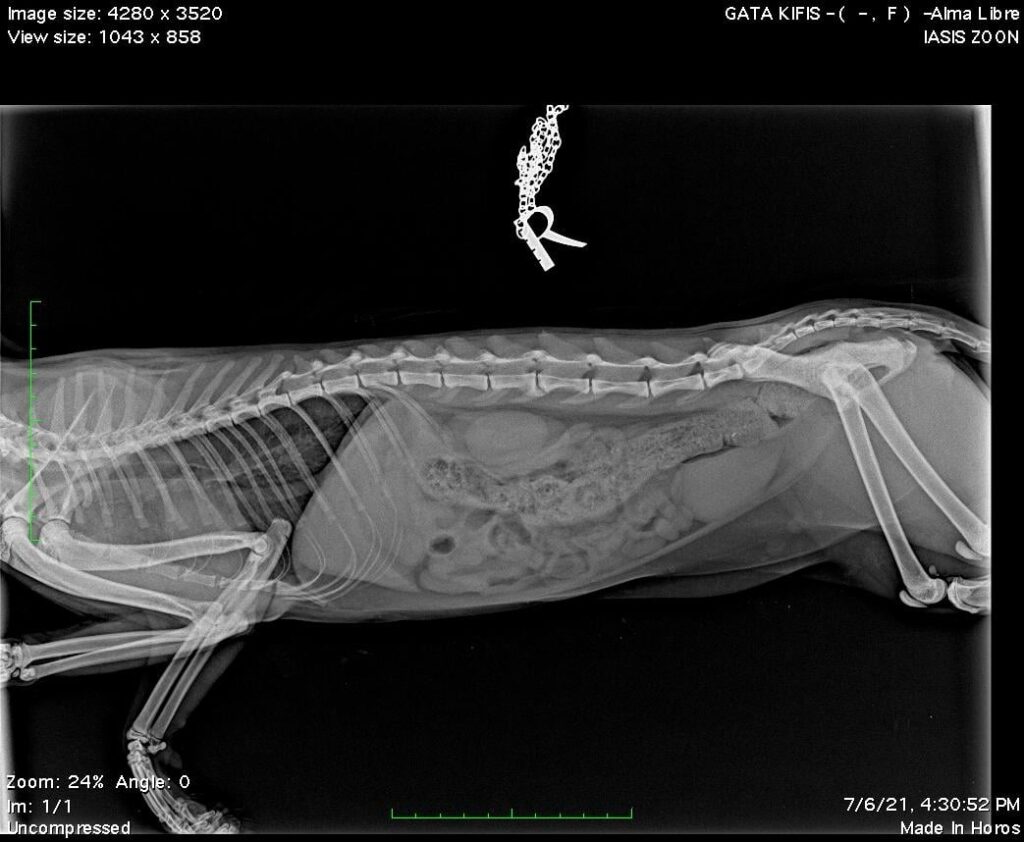

Η γατούλα μεταφέρθηκε στο ΙΑΣΙΣ ΖΩΩΝ. Μπορεί να μην είχε τίποτα σπασμένο αλλά είχε εμφανή εξωτερικά τραύματα και αιμορραγία στο κεφάλι, κάτι που όμως δεν επηρέαζε την υγεία της. Οπότε πήρε εξιτήριο ώστε να μείνει λίγες μέρες σε σπίτι και να επανενταχθεί.

“Το κόστος της ακτινογραφίας, της νοσηλείας και των φαρμάκων που έλαβε η γατούλα είναι στα 44 ευρώ. Παρακαλούμε βοηθήστε με την κάλυψη των εξόδων αυτών επικοινωνώντας με το κτηνιατρείο για στοιχεία λογαριασμού αναφέροντας τη γάτα για την οποία προορίζονται (Gata Kifi / Alma Libre).